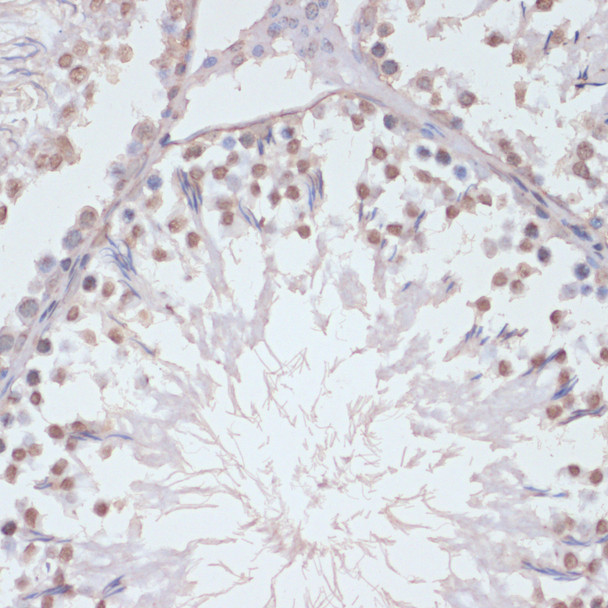

Western blot analysis of lysates from NIH/3T3 cells using Phospho-p38 MAPK-T180/Y182 Rabbit pAb (CABP1310) at 1:500 dilution. NIH/3T3 cells were treated by UV at room temperature for 1 hour.Secondary antibody: HRP Goat Anti-Rabbit IgG (H+L) (CABS014) at 1:10000 dilution.Lysates/proteins: 25 μg per lane.Blocking buffer: 3% nonfat dry milk in TBST.Detection: ECL Basic Kit (AbGn00020).Exposure time: 180s.